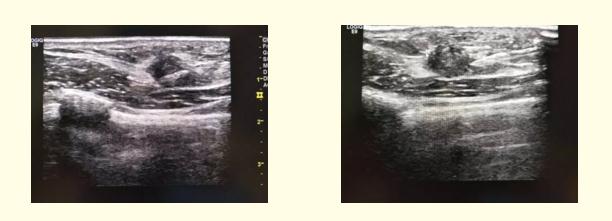

近日,彩超室成功为一患者实施了乳腺占位穿刺活检术,经病理证实为浸润性导管癌Ⅱa期。

该患者为老年女性,查体发现右侧乳腺占位,来到我院就诊治疗,行超声检查,超声报告为:右侧乳实性占位BI—RADS 4b类(高度怀疑恶性病变)。建议行乳腺穿刺活检以确定诊断及分期。彩超室邵宏增主任和高珊珊医师在超声引导下,为该患者实施了乳腺穿刺活检术,超声全程精确定位引导,手术顺利。病理结果:右侧乳腺侵润性导管癌Ⅱa期。明确诊断,可为临床选择更合理的系统治疗方案。